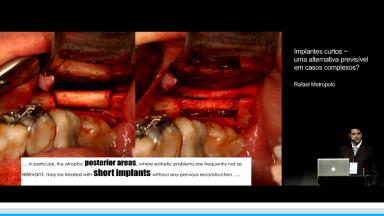

Implantes curtos – uma alternativa previsível em casos complexos?

Apresentação traz uma revisão teórica sobre o potencial e previsibilidade dos implantes curtos ilustrados com uma série de casos desafiadores, com o objetivo de simplificar a técnica cirúrgica e protética com segurança e resultados previsíveis. Os casos apresentados trazem uma discussão clínica sobre as indicações, possíveis motivos de falhas e sugestões de soluções para casos limites e complexos.

- discutir a indicação de implantes curtos

- identificar casos com potencial para serem tratados com implantes curtos

- descrever situações clínicas e protéticas favoráveis e desfavoráveis